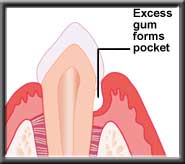

In a few cases, the swollen gums may not shrink back to normal after the infection is removed, and must be trimmed by the dentist with a gingivectomy. Otherwise the swollen gum makes removal of plaque by the patient very difficult, and the problem starts again.

Pocket reduction with a gingivectomy |